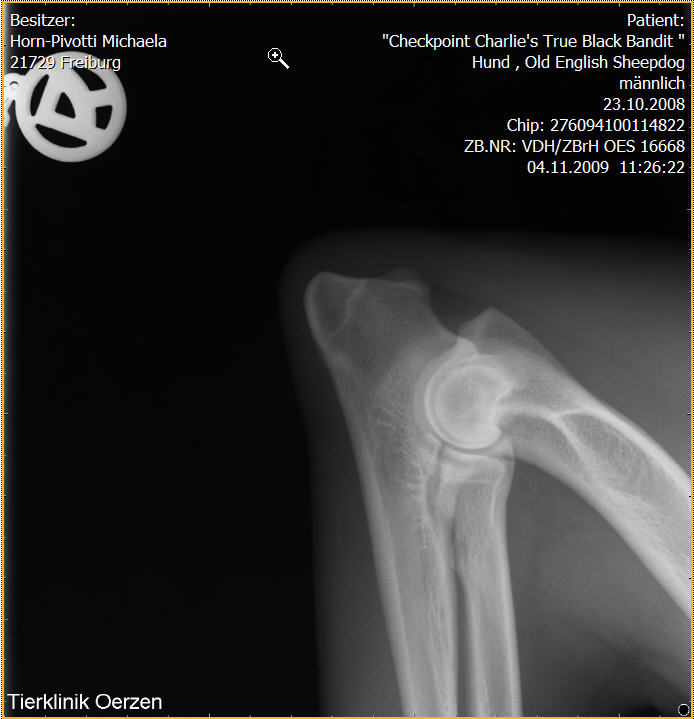

Röntgenaufnahmen HD/ED “Checkpoint Charlie’s True Black Bandit”